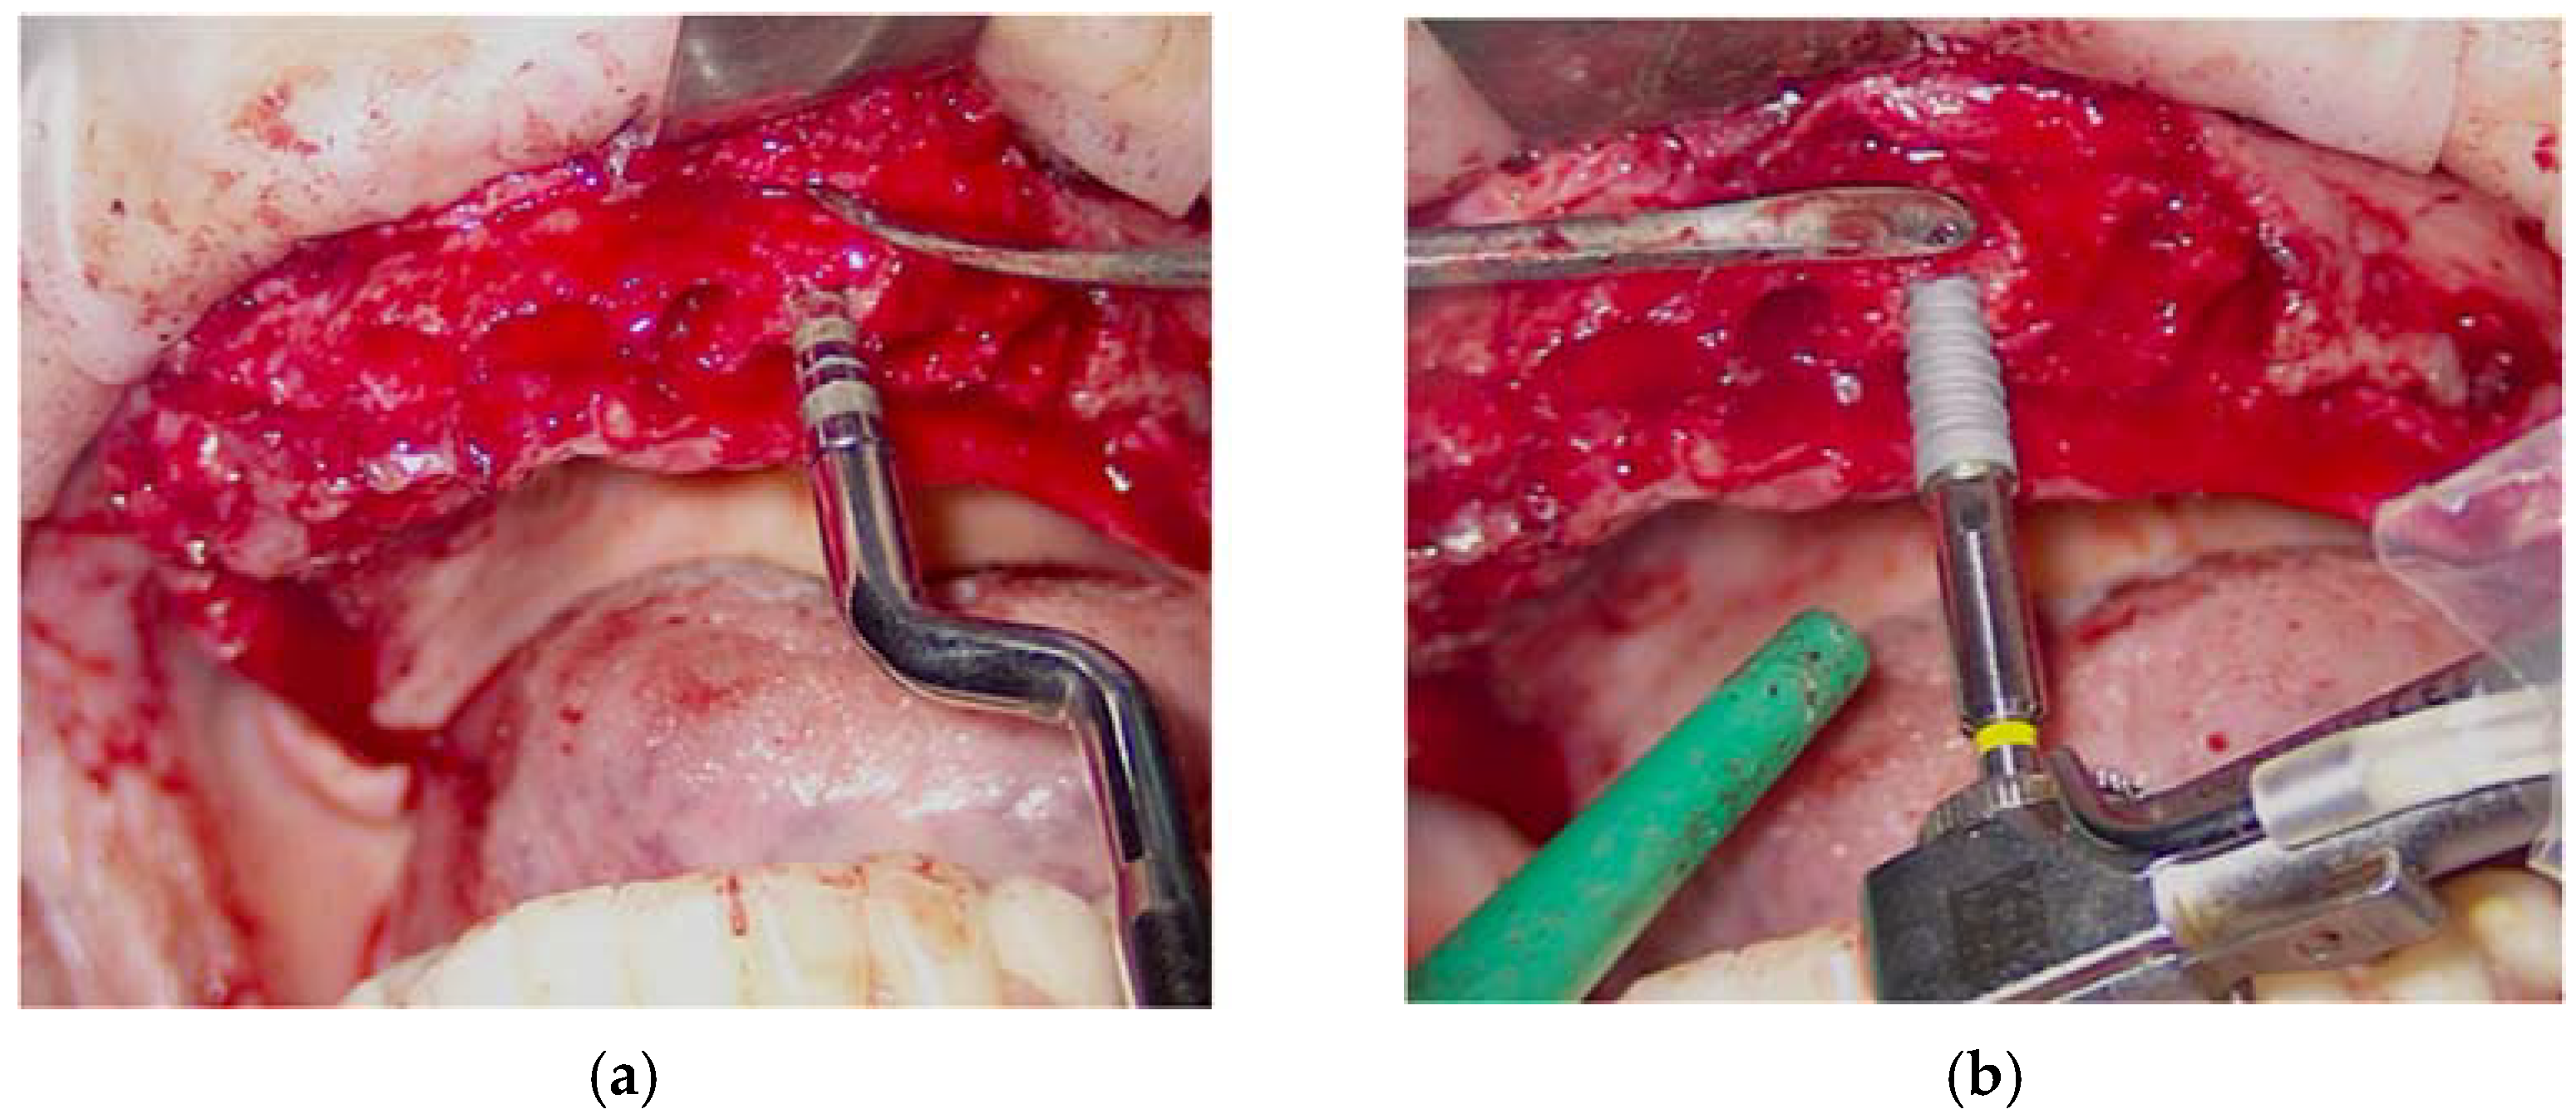

Surgical Procedure